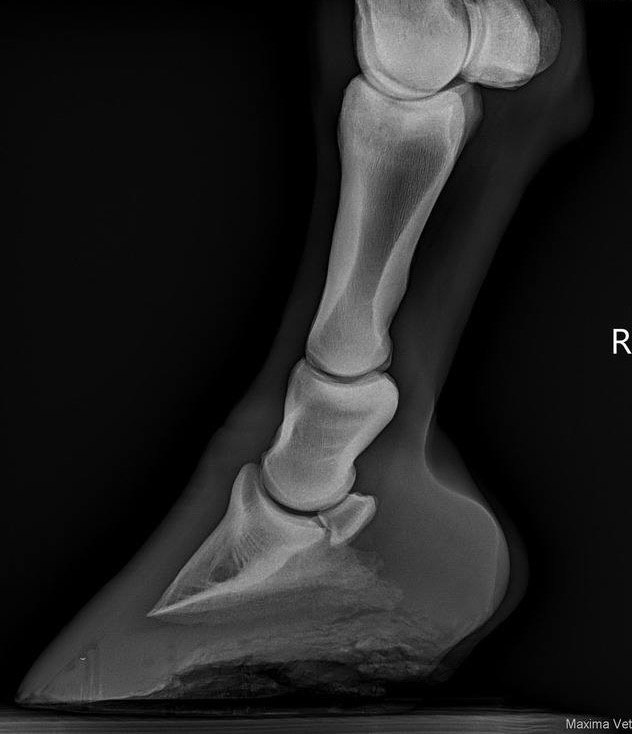

ПРИМЕРЫ МРТ-снимков с комментариями:

Данные изображения отражают отек - синовит в копытном суставе и нарушение в суставном хряще копытного сустава. Такую лошадь можно пролечить с вязкоупругими гелями, противовоспалительными и сохранить на шаговой нагрузке до улучшения и затем постепенно вернуть в работу.

Здесь очевидна травма медиальной коллатеральной связки копытного сустава с вовлечением в патологический процесс венечной кости. Такая лошадь, конечно, имеет артрит и синовит копытного сустава, но это вторично к энтезопатии связки. Лечение в данном случае будет необходимо проводить с физиотерапией, инъекциями в сустав и полным покоем в деннике.

На этих снимках у лошади хронический синовит путового сустава. Выявленные отклонения отображают хроническое изменение плотности кости - склеротизацию, а также изменение конфигурации суставного блока. В медицинской практике такому пациенту предлагают заменить сустав, так как присутствуют хронические отклонения, которые не позволяют суставу работать в полном объеме. Для лошадей такая процедура еще не доступна. Поэтому так важен ранний мониторинг повреждения чтобы управлять процессом и не доводить до точки невозврата.